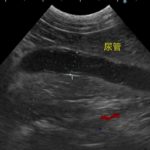

かかりつけ医で定期的に超音波検査で腎結石のモニターをしていたところ、急に腎盂が拡張してきたので早急に対応して欲しいと連絡がありました。尿管結石により尿路閉塞が起こっていました。マイクロサージェリーで尿管を2箇所切開し、尿管結石を摘除しました。術後の狭窄予防に一時的に尿管ステントを留置しています。術後翌日から、腎盂拡張は解消しましたが、術後の経過により、生体にとって異物となる尿管ステントは抜去する予定です。